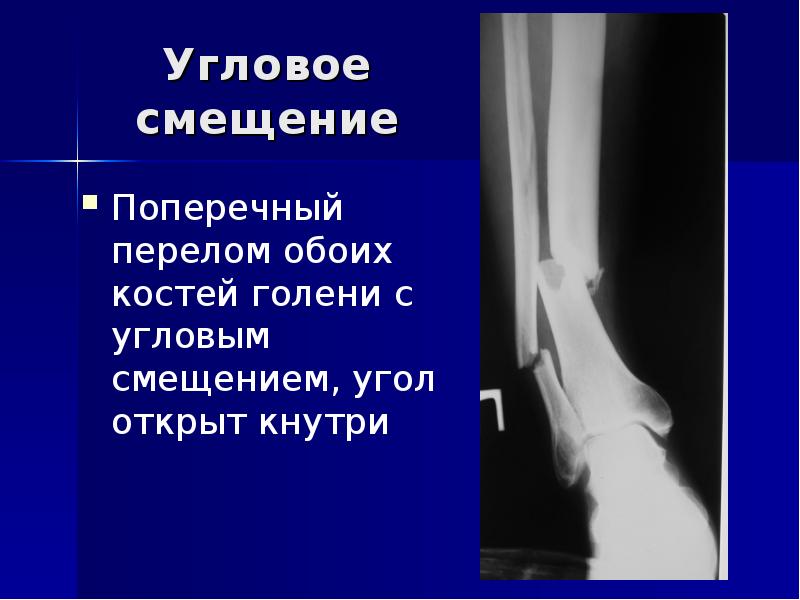

23. Угловое смещение

Поперечный

перелом обоих

костей голени с

угловым

смещением, угол

открыт кнутри

Слайд 23

Описание слайда:

Угловое смещение

Поперечный перелом обоих костей голени с угловым смещением, угол открыт кнутри